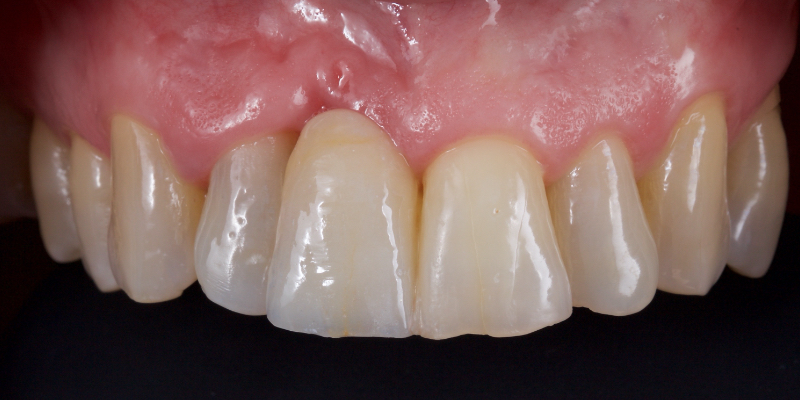

Take Arthur, a 76-year-old man who presented with a vertical root fracture of his upper left central incisor. His medical conditions precluded his request for an implant, so he agreed to the proposal for an adhesive bridge instead.

The tooth was extracted and for four months the pontic site was conditioned with a removable Essix-type of denture (Fig. 1).

An e.max (lithium disilicate), one-wing (adjacent central being the retainer) bridge was placed, which resulted in an acceptable outcome (Figs. 2-4) that was more timely and at a lower financial and biological cost to the patient than the implant Arthur initially thought he wanted.